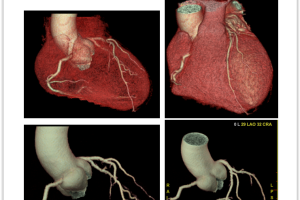

MSCT koronarografija je brza, precizna i neinvazivna metoda snimanja koja nam omogućava jasan uvid u stanje vaših koronarnih arterija. Pomoću najsavremenije CT tehnologije, možemo detaljno analizirati protok krvi i identificirati eventualna suženja ili blokade.

3. Precizna dijagnostika: Najsavremenija tehnologija omogućuje nam otkrivanje čak i najmanjih promjena u koronarnim arterijama.